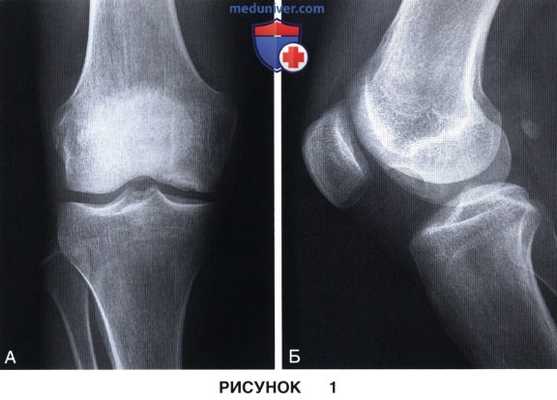

7. Рентгенография:

• Информативна в отношении локализации и оценки размеров поражения

• В дополнение к стандартным рентгенограммам в прямой и боковой проекциях выполняется рентгенография в заднепередней проекции при сгибании до 45° и аксиальная рентгенография надколеннико-бедренного сустава (рис. 1)

• Большинство очагов РОХ видны на рентгенограмме в боковой проекции в пределах зоны, ограниченной линией, являющейся продолжением задней кортикальной пластинки бедра, и линией Blumensaat

• У пациентов с незрелой костной системой обязательна рентгенография противоположного коленного сустава, даже если он пациента не беспокоит (рис. 2); лечение бессимптомных поражений остается предметом споров и чаще всего не рекомендуется